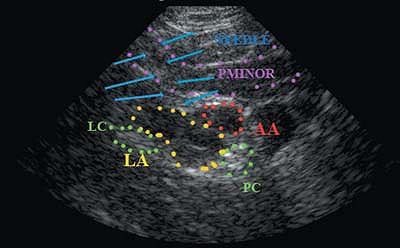

|

Figure 43-5.

The tip of the needle is in the pectoralis minor muscle and the local anesthetic is collecting above the lateral cord. LA, local anesthetic; AA, axillary artery; LC, lateral cord of the brachial plexus. |

![]() |

Figure 43-6.

The tip of the needle is below the pectoralis minor and the local anesthetic is collecting around the axillary artery, pushing the lateral cord more laterally. LA, local anesthetic; AA, axillary artery; LC, lateral cord; PC, posterior cord; PMINOR, pectoralis minor. |